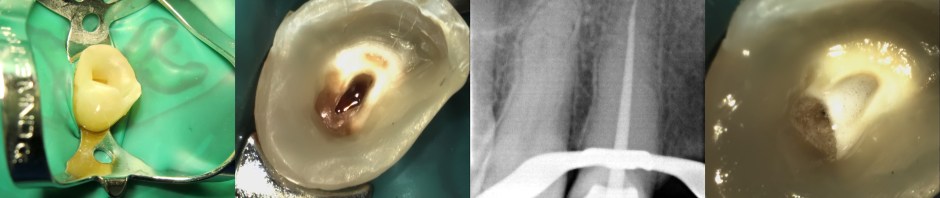

Endodontic and Fiber Post placement on upper right canine

This case will emphasize on the length of fiber post in post endodonticallh treated tooth.

This case protocols: Shaping was done with Mtwo files (VDW) with clockwise reciprocal motion (imate2C endomotor from Denjoy). Cleaning with sodium hypochlorite 5,24% (generic), EDTA 18% sol (ultradent), CVC guttapercha with resin based sealer. Fiberpost cemented with resin cement (relyx u200 – 3M), and core build up with bulkfill composite (filtek bulkfill – 3M). Xray evaluation with vistaray 7.1 sensor (durr) showed intact marginal integrity and homogeneous body.